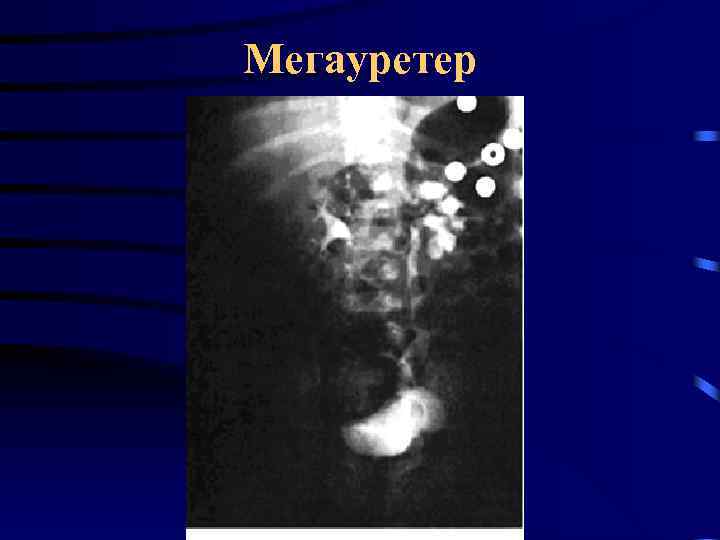

Аномалии мочеточника • • • Атрезия мочеточника Удвоение мочеточника Эктопия устья мочеточника Уретероцеле Ретрокавальный мочеточник Стриктура лоханочно-мочеточникового сегмента • Мегауретер

Аномалии мочеточника • • • Атрезия мочеточника Удвоение мочеточника Эктопия устья мочеточника Уретероцеле Ретрокавальный мочеточник Стриктура лоханочно-мочеточникового сегмента • Мегауретер

Стриктура ЛМС Мегауретер

Стриктура ЛМС Мегауретер

Мегауретер

Мегауретер